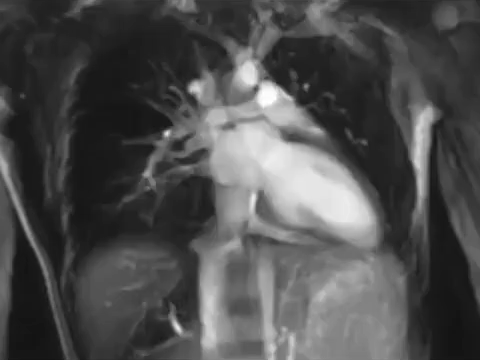

É certo que o simples, o que nós vemos, já é profuso em beleza – mas consideremos o que se imerge em nós, por detrás deste tecido entediante e antes de sequer chegarmos ao ínfimo, e descobrimos uma orquestra divina de cordas e tubas e sopros e órgãos. E o maestro, lá em cima, com a sua batuta – chamaram-lhe espinha – regula os tempos, os volumes, os fins e os começos.

Cada ciclo tem 0.8 segundos com sístoles e diástoles, contracções e relaxamentos, abertura e encerramento coordenado das válvulas atrioventriculares (tricúspide e mitral) e semilunares (pulmonar e a aórtica).

E, se aquém da perfeição, cada um destes fenómenos tem as suas próprias patologias: arritmias, valvulopatias, anginas, cardiomiopatias.